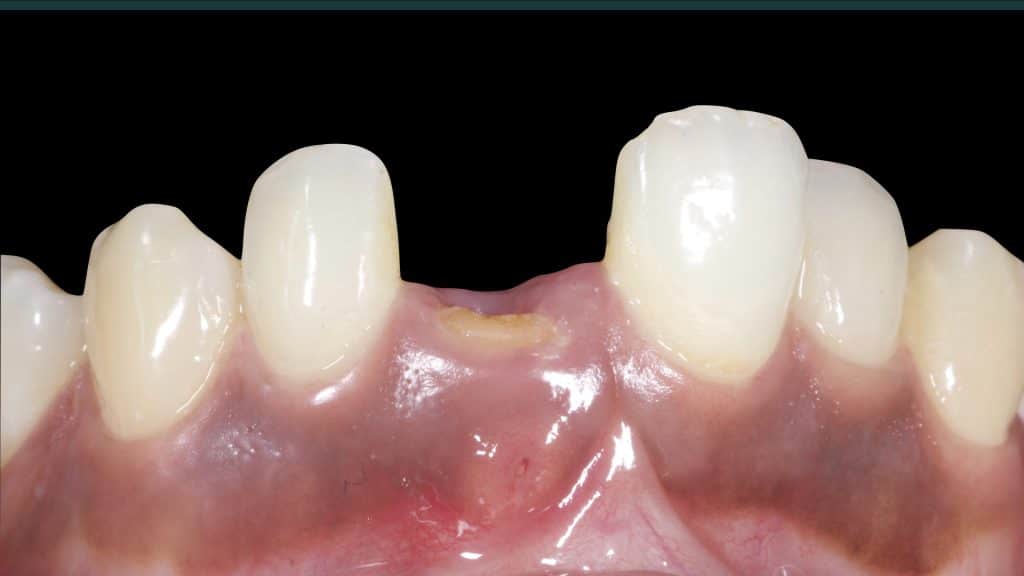

20 days post-op after suture removal